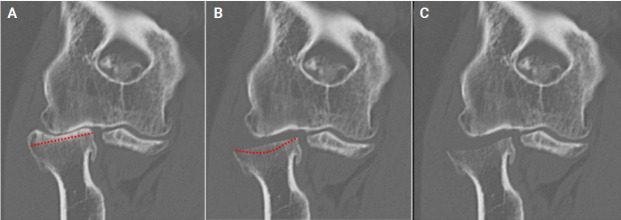

Background: Radiocapitellar arthritis can cause pain, loss of motion, and impaired elbow function. Current surgical treatment options are limited. We have developed an original and simple surgical technique to address this, called arthroscopic matched osteoplasty of the radial head (AMOR). In AMOR, the radial head is partially resected and recontoured to match the capitellum and decompress the degenerate radiocapitellar articulation while preserving the ulnohumeral articulation where the cartilage is usually well preserved.

Results: Between 2017 and 2021, eight consecutive patients underwent AMOR as part of an arthroscopic osteocapsular arthroplasty procedure. Radiographically, the mean radiocapitellar joint space improved from an average of 1.7 mm to 4.6 mm. Clinically, the mean pain score decreased from 8/10 to 3/10. Six of the eight patients (75%) were satisfied with their results. In two cases, initial improvement following surgery lasted less than 1 year, and one of these patients underwent total elbow arthroplasty for painful ulnohumeral osteoarthritis. There were no complications of surgery recorded.